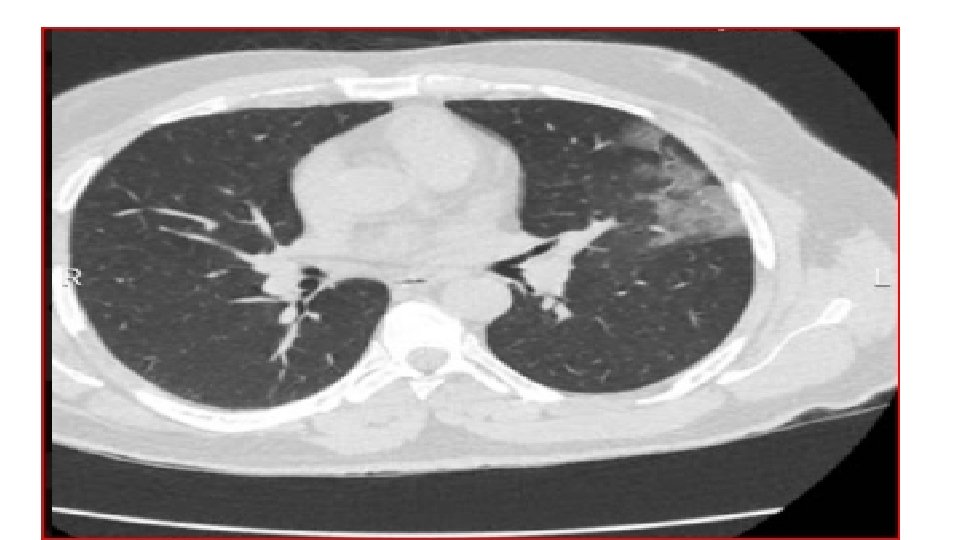

Chest X-ray An X-ray : look for signs of inflammation in chest. If inflammation is present, the X-ray can also inform about its location and extent.

In COVID-19 pneumonia Leukopenia in ~70% of hospitalized patients. LDH may be modestly elevated. LFTs elevated more commonly than in typical Community-Acquired Pneumonia cases. Chest CT may show ground-glass opacities that may evolve into consolidation or ARDS. Findings appear to peak at 10 d of illness, resolution begins after day 14. CT may show lung findings (such as ground-glass opacities) before the development of symptoms. Among hospitalized patients, about one-third need to be in the ICU/intubated with an ARDS picture. Elevations in IL-6 (> 40– 100), CRP (> 10 x normal), ferritin (> 1000) suggested correlating with a cytokine release syndrome-like picture and impending ARDS.